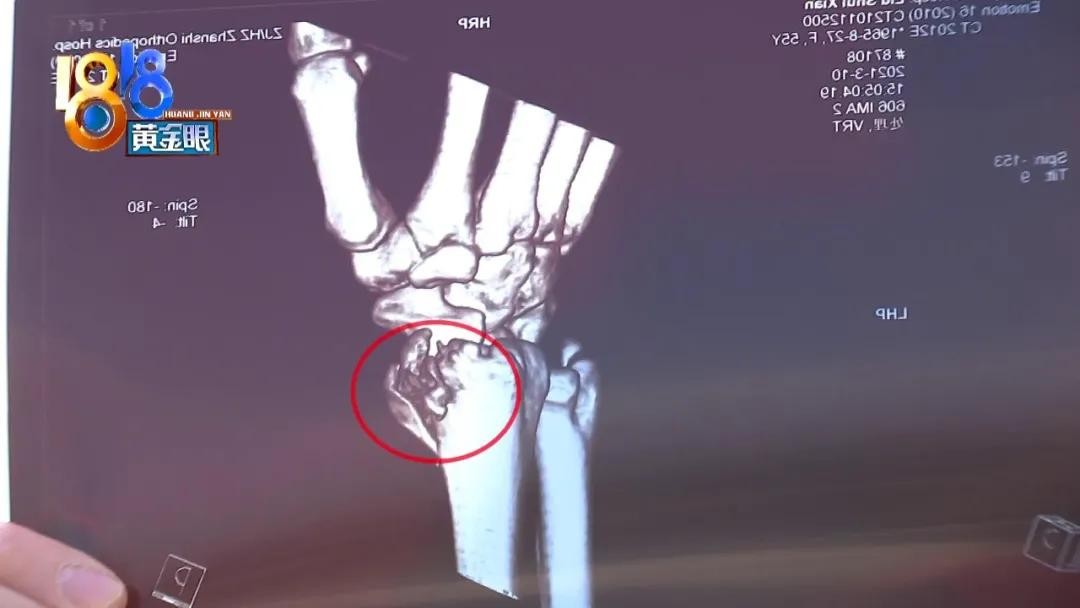

在杭州石祥路一家骨伤科医院的停车场,记者见到了周先生的母亲,左手手腕上了夹板,医院拍片结果显示“左桡骨远端粉碎性骨折”。